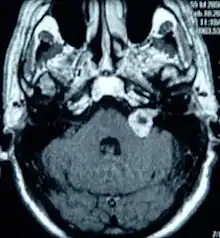

Resonancia magnética con contraste.

Así, si el índice de sospecha por los síntomas y por la audiometría tonal es muy alto, se solicitará una resonancia magnética craneal, con un contraste especial denominado Gadolinio, que es la técnica más específica existente hoy día y que ha revolucionado el diagnóstico de los neurinomas del octavo par craneal, permitiendo detectarlos con tamaños muy pequeños.